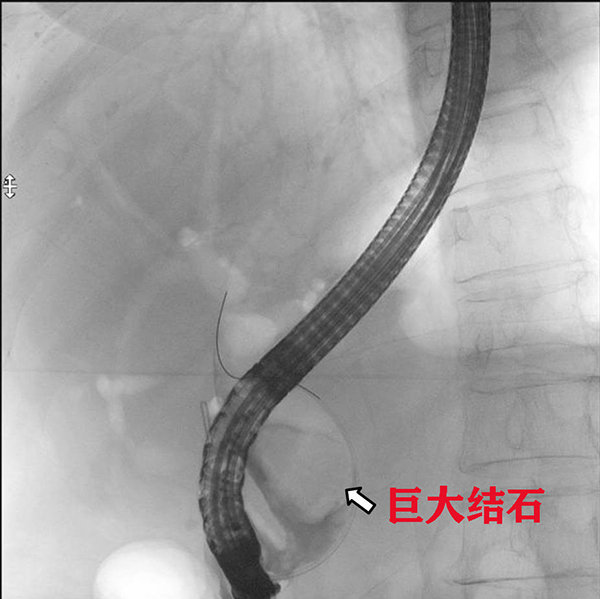

醫(yī)生與患者家屬溝通病情及簽署手術(shù)同意書(shū)后,為都奶奶實(shí)施了急診ERCP。術(shù)中,消化內(nèi)科副主任蔡懷陽(yáng)、特聘專(zhuān)家李運(yùn)澤認(rèn)真研讀了患者的CT影像及ERCP術(shù)中造影影像,發(fā)現(xiàn)患者膽總管結(jié)石巨大,但質(zhì)地不硬,可以進(jìn)行ERCP取石。醫(yī)生們靈活采取多種碎石、取石技術(shù),最終成功將結(jié)石全部取出。都奶奶的膽道梗阻得到成功解除,整個(gè)手術(shù)過(guò)程非常順利。

此次從都奶奶身體里取出的膽總管結(jié)石大小約2.5x4.0cm,是醫(yī)院開(kāi)展ERCP十余年來(lái)取過(guò)的最大的結(jié)石,在柳州乃至廣西也很少有成功取出如此巨大膽總管結(jié)石的病例。術(shù)后,患者體溫、血壓立即恢復(fù)正常,術(shù)后第二天即可進(jìn)食、下床活動(dòng),第六天痊愈出院。在這場(chǎng)與死神爭(zhēng)搶生命的戰(zhàn)爭(zhēng)中,消化內(nèi)科成功克服困難,獲得了患者和家屬的信任與感激!